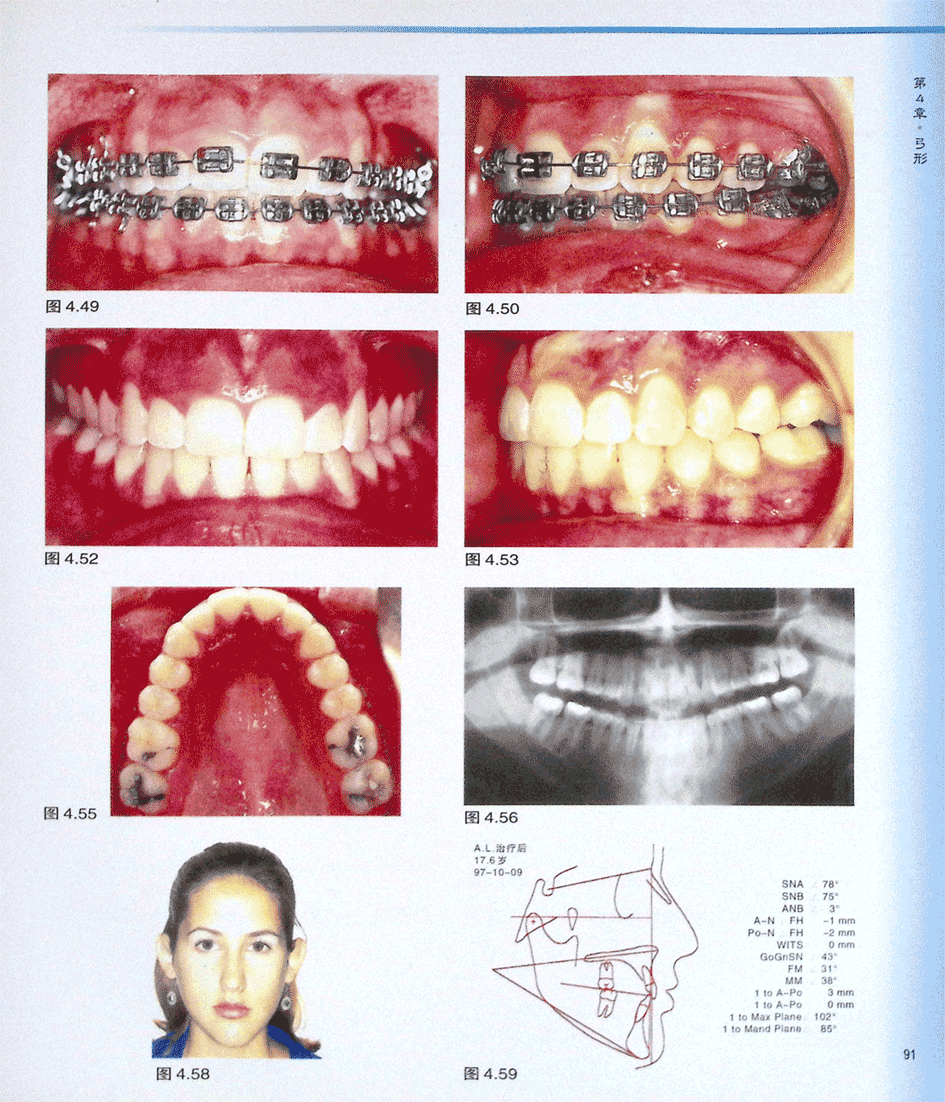

病例AL(二)